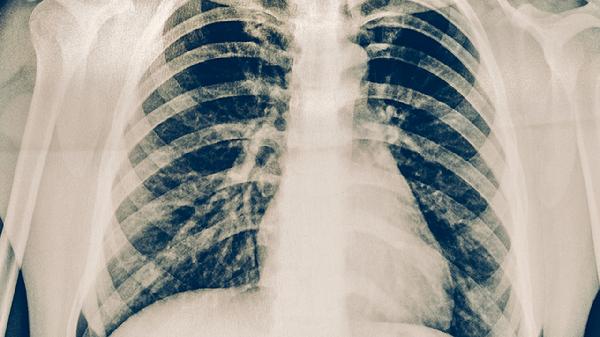

肺结核可能通过体检发现,但普通体检项目可能无法直接检出肺结核。肺结核主要通过胸部X线检查、痰涂片检查、结核菌素试验等方法诊断,常规体检若未包含这些项目则难以发现。

普通体检通常包括血常规、尿常规、肝功能等基础项目,这些检查无法直接诊断肺结核。部分体检套餐包含胸部X线检查,可能发现肺部异常阴影,但需结合痰检或结核菌素试验进一步确诊。肺结核早期症状不典型,可能仅出现低热、乏力等非特异性表现,易被忽视。体检时若未主动告知医生结核病接触史或疑似症状,漏诊概率更高。

肺结核确诊需依赖专业检查。痰涂片找抗酸杆菌是诊断开放性肺结核的金标准,结核菌素试验可辅助判断感染状态,胸部CT能更敏感地发现早期病灶。对于高危人群如密切接触者、免疫力低下者,即使体检结果正常,出现咳嗽咳痰超过两周也应专项筛查。部分非活动性肺结核或肺外结核,常规体检更难发现。